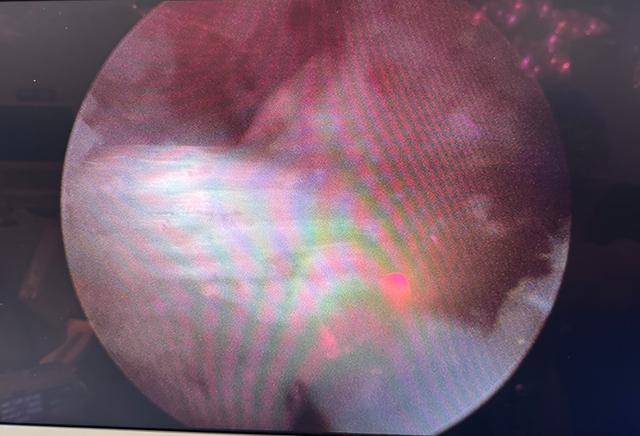

术后镜下影像(人工韧带走向良好)